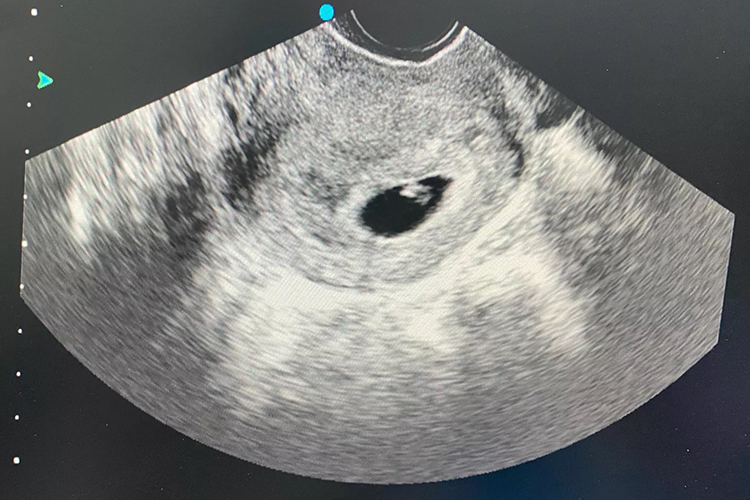

水滴形孕囊是怀孕期间进行超声检查时,所显露的一种征象,说明孕囊不是常见的圆形或卵圆形,可能与瘢痕妊娠有关。

正常孕囊超声征象一般为圆形或卵圆形。当出现瘢痕妊娠时,尤其是孕囊大部分位于宫腔,小部分位于切口瘢痕处时,可出现孕囊变形、被拉长的情况,使孕囊呈水滴形,同时超声可见瘢痕附近的子宫肌层存在丰富的血流信号。